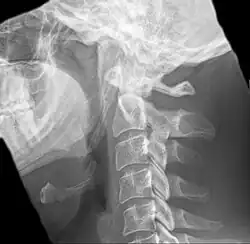

Imaging is important and is diagnostic. Visualizing the styloid process on a CT scan with 3D reconstruction is the suggested imaging technique.[13] The enlarged styloid may be visible on an orthopantogram or a lateral soft tissue X ray of the neck.